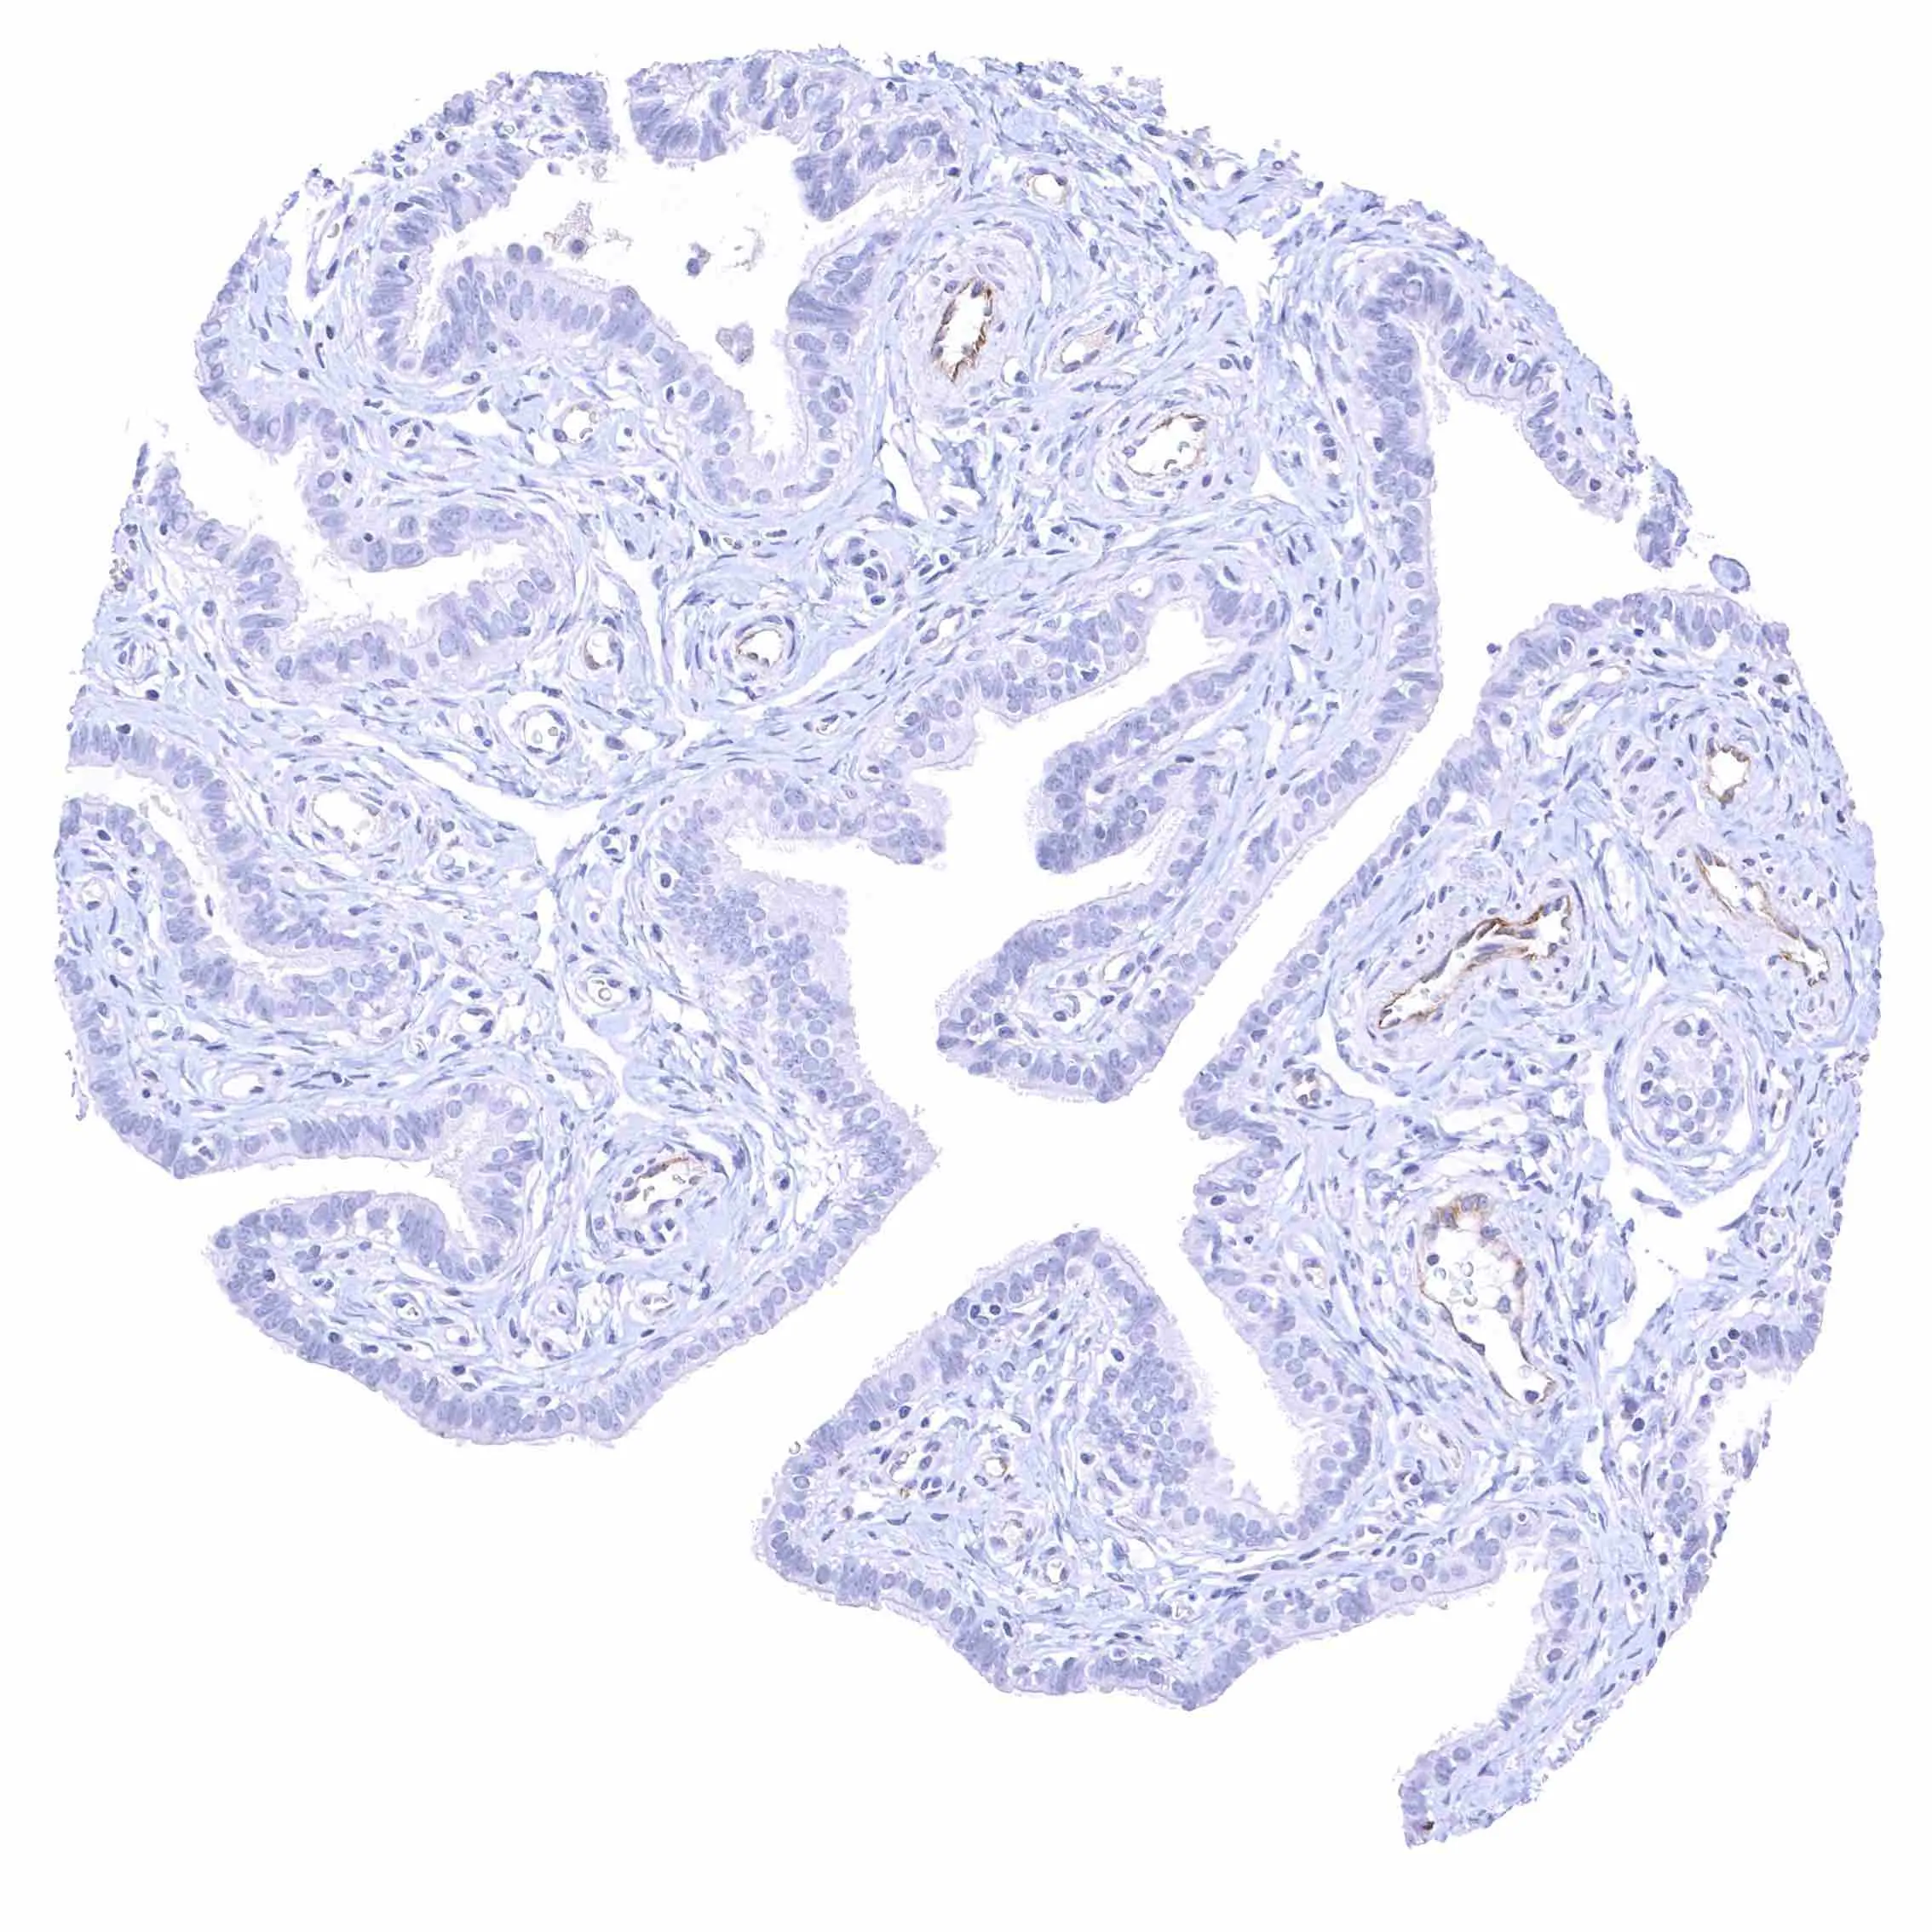

Seminal vesicle – Intense membranous NPR-C staining at the luminal cell border of endothelial cells of small blood vessels.